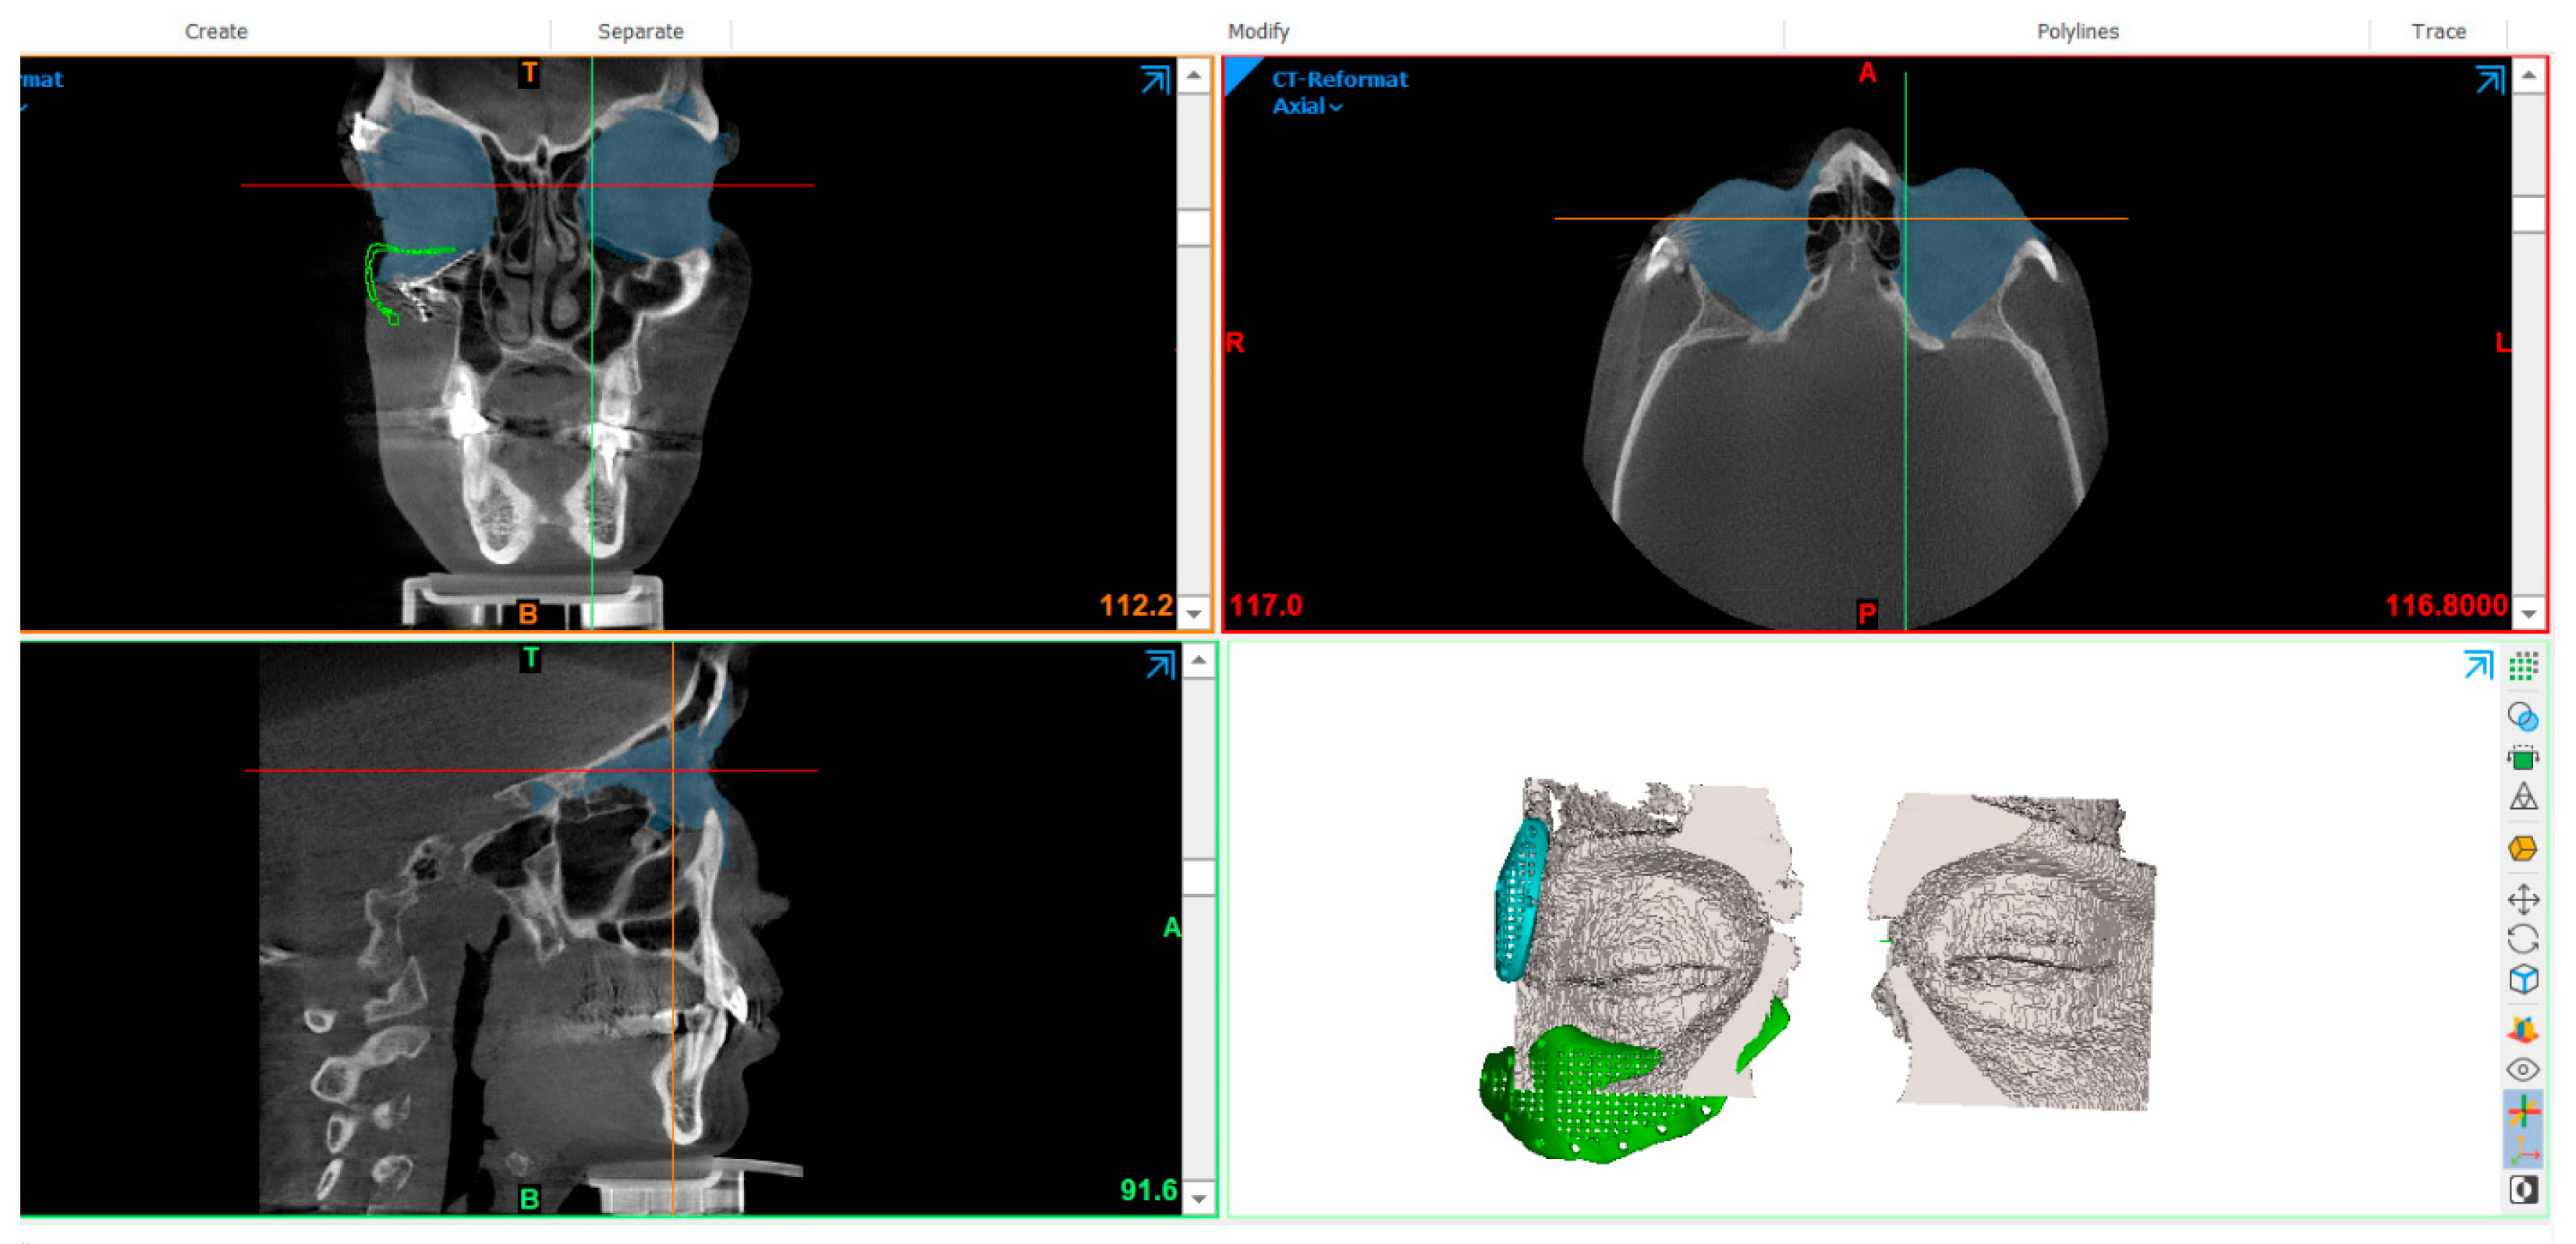

2.2. Skull Model Generation

2.3. PSI Design

2.4. Virtual Planning of Patients-Specific Implants

2.7. Models Registration